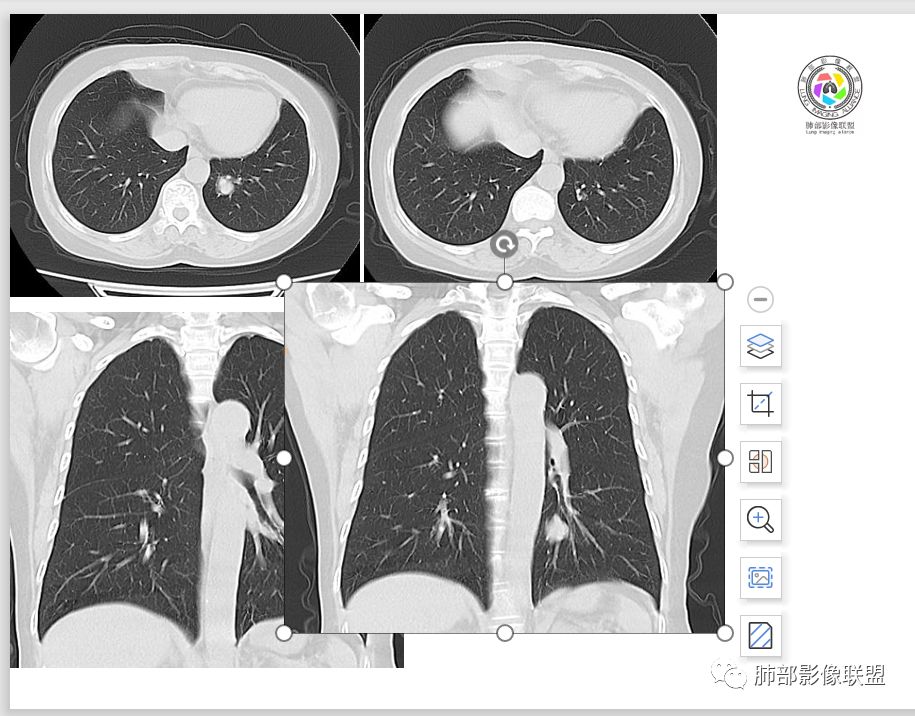

1.肺内如此大小的周边较光滑的孤立结节影或块影,密度较均匀的,一般会想到硬化性肺细胞瘤、错构瘤、小细胞癌、大细胞癌、类癌,以及单发转移灶等。

2.边缘光整,坏死不明显,未显示阻塞性炎症或不张,女性患者,肺鳞癌不支持。

3.缺乏典型深分叶及毛刺,强化不显著,似乎也缺乏肺腺癌的影像学特点。

4.未见脂质密度及钙化,强化程度等均不支持错构瘤。

5.同样病灶轻到中度强化也不支持类癌及大多数的硬化性肺细胞瘤(血管瘤样区为主)。

后者不能排除,毕竟不是所有的硬化性肺细胞瘤强化都那么显著。

6.转移瘤缺乏相关临床支持。

7.病灶的形态及强化程度都不能排除小细胞癌及大细胞癌,纵隔尤其是隆凸下未见增大淋巴结似乎不符合小细胞癌等的生物学行为。

未解之迷有:

1.图片未能提供病灶与支气管的确切关系,支气管截断有助于大细胞癌或腺癌的判断,管腔狭窄有助于小细胞癌的判断。

2.CT扫描到手术病病理相隔多久?影像并未显示隆凸下增大的淋巴结。

3.图像显示的结节影,它一定是该患者小细胞癌的发祥地吗?外围存在隐匿病灶吗?可惜我们没有更加全面的资料,殊为憾事!